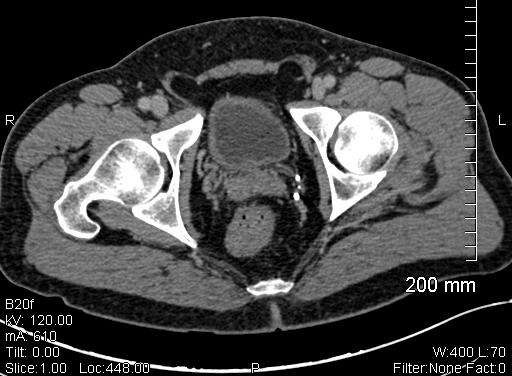

In the past 20 years there have been considerable improvements in the treatment of prostate cancer. As it is across all radiation oncology, techniques have evolved from conventional external beam radiation therapy (EBRT), to more targeted therapies that are delivered in fewer visits. One of the latest notable trends in radiotherapy is the emergence of real-time image guidance for intensity-modulated radiation therapy (IMRT). For prostate cancer, radiotherapy is often deployed in conjunction with surgery (prostatectomy) or as curative therapy, depending on the stage of disease. As these new techniques emerge, it becomes more important for clinicians to identify which ones work most effectively and for which patients.